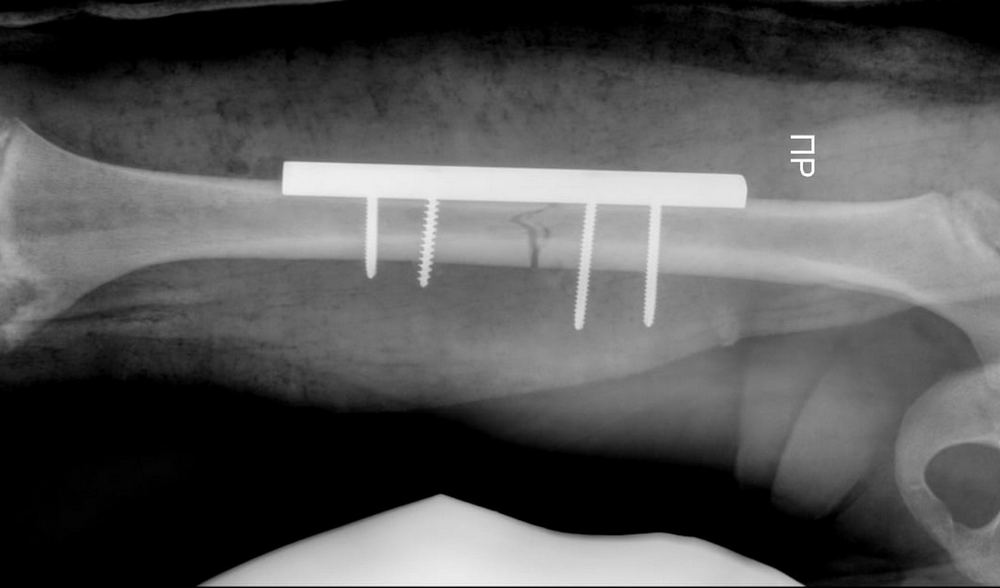

Врачам на этот раз пришлось повторно проводить операцию.

В течение часа детский хирург Курман Кайранов успешно заменил металлический на более современный гибкий стержень.

- Преимущество гибкого стержня заключается в том, что теперь при переломах больше не требуется делать большие разрезы в конечностях для установки фиксирующих стержней. Достаточно лишь сделать разрез в один сантиметр и вводить гибкий стержень под рентгеновским контролем, - рассказал Курман Кайранов.